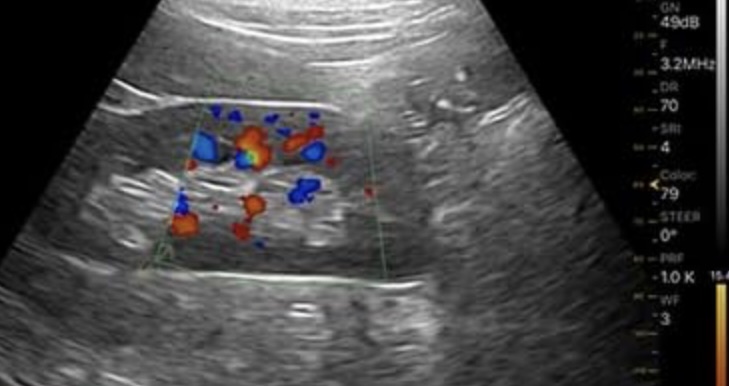

Не обязательно рентген, он опасен.

Могут помочь визуальные ультразвуковые дефектоскопы. Вот картинка YFD200 с eBay, цена меньше 2000$:

Причем нам не нужна высокая четкость - вот кругляк батарейки, вот дорожки плат, вот детали итп. |

И вот еще, что можно пробовать - ветеринарная ультразвуковая приставка к смартфону за 1500$:

На Амазоне.